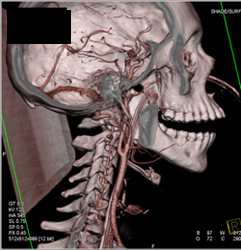

Carotid Artery Stenosis